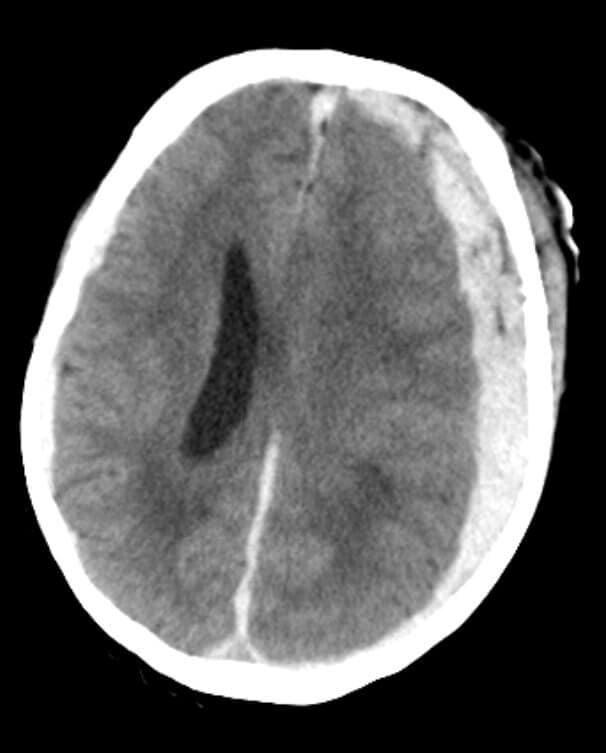

Soy médico especialista en cirugía neurológica y columna vertebral, con la experiencia profesional en el uso de la tecnología más innovadora a nivel mundial, para lograr los mejores resultados en las enfermedades del cerebro y la columna vertebral.

Soy médico especialista en cirugía neurológica y columna vertebral, con la experiencia profesional en el uso de la tecnología más innovadora a nivel mundial.